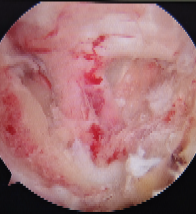

内镜下颈椎后路手术一项脊柱外科高精尖的微创技术,技术难度大、风险高、学习曲线长,为了不断提高技术,采众家所长,确保手术安全与效果,我院骨科脊柱外科团队特别邀请国内脊柱微创AUSS 技术创始人,云南昆明医科大学第一附属医院宋恩教授进行手术演示。手术于 2023 年 11 月 23 日在全身麻醉下进行,采用先进的 AUSS 技术,通过内镜下精准操作,顺利完成颈 6-7 椎间盘切除及神经减压。

相较于传统开放手术,内镜下微创手术具有创伤小、出血少、恢复快等显著优势。AUSS是Arthroscopic-assisted Uni-portal Spinal Surgery的简称,中文翻译为单孔脊柱内镜技术(或关节镜辅助单孔脊柱手术),其工作通道与观察通道在同一软性切口内手术,具有减压范围广、操作空间大、自由,是开放手术内镜化的体现,不同内镜技术的结合:关节镜的三角操作以及后路同轴内镜的同轴摆动、旋转。是目前脊柱微创较为先进的一项技术。手术在高清内镜视野下避开重要神经血管,精准清除突出的椎间盘组织,彻底解除对神经根的压迫,整个手术过程顺利,耗时短、创伤小,达到了预期的治疗效果。